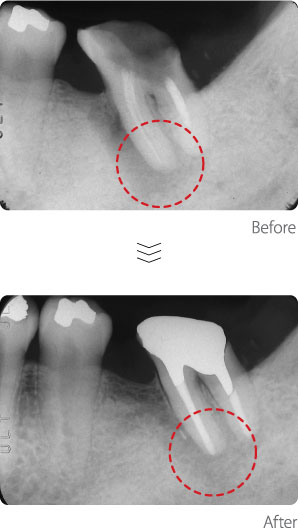

根管治療〈Case1〉

神経の管を通じて、歯根から根の先の骨の中にまで細菌が入り込んで炎症を引き起こし、骨が溶けてきています。根の周囲の白い部分が骨にあたりますが、根の周囲の骨が溶け、黒く写ってきています。根管治療後は炎症が無くなり、骨が再生して、黒い部分が無くなってきています。